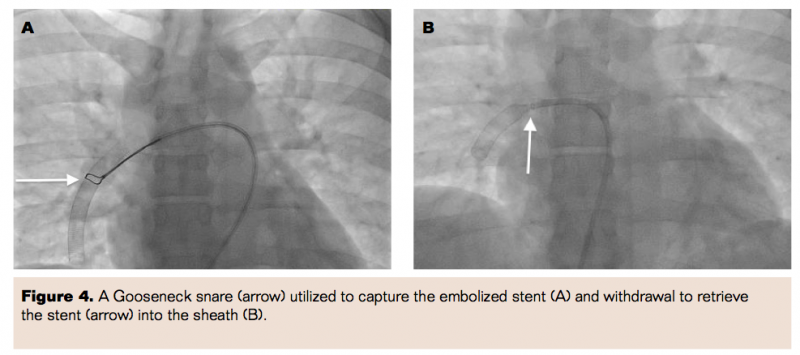

Access was obtained in the right femoral vein, and iliocaval venogram revealed brisk flow with no evidence of thrombosis and normal caliber iliac veins. A balloon-tipped PA catheter was used to demonstrate elevated right heart pressures with PA mean pressure of 35 mmHg. Angiogram of the PA confirmed the presence of a stent lodged in the right lower lobe branch of the PA (Figure 3). A 7 Fr Pinnacle Destination sheath (Terumo) was then advanced selectively into the right PA, and a 25 mm Gooseneck snare (Covidien) was used to capture the embolized stent edge (Figure 4a). Persistent negative backward pressure on the snare with concurrent positive forward pressure on the sheath was utilized to gradually retrieve the embolized stent into the sheath (Figure 4b) and subsequently externalized from the sheath (Figure 5). Repeat selective PA angiogram revealed persistent clot burden in the right lower lobe branch of the PA (Figure 6). An ultrasound-enhanced thrombolysis catheter (EkoSonic Endovascular System; BTG International) was positioned within the right lower lobe branch of the PA and catheter-directed thrombolysis (CDT) initiated at 1 mg/hr of tPA infusion through the catheter (Figure 7). The thrombolysis catheter was removed after 24 hours and the patient subsequently initiated on anticoagulation with warfarin and discharged home when therapeutic levels had been reached. She was seen in follow-up in 1 month when a repeat CT revealed resolution of the pulmonary embolism (Figure 8) and no residual injury from the embolized stent.

It appears in most cases of stent migration that inappropriate stent dimensions and malposition may be major contributing factors. Several techniques have been used in the retrieval of embolized stents. Initially, use of a basket or self-made wire snares were primary modalities.11 Baskets are useful when one end of a foreign object is free in the vessel lumen. Entrapment using a basket is difficult in tortuous or angulated vessels.12 The forceps technique has also been used but often requires a venous cut-down and is potentially traumatic, causing lacerations and perforations.13 Balloon catheters have also been used to capture the stent and reposition it in an alternate vascular segment. In one of the largest single-center trials investigating retrieval of migrated stents, balloon catheters were the predominant method used with the greatest success.14 However, with self-expanding stents, this is less successful because of the tendency of the stent to assume the nominal diameter in the vascular lumen.15

The nitinol stent is unable to expand beyond its nominal diameter, has a high degree of self-expandability, and has a larger mesh size; all of these characteristics make retrieval of such stents difficult. Use of a nitinol snare has become the method of choice for stent removal.16 Capturing and compressing the stent often damages the stent, and unprotected passage may damage the vessel wall; therefore, use of a larger overlying catheter with the snare allows better control of the snare and atraumatic withdrawal of the stent.13 Significant success has been found in the use of snares for foreign body retrieval in a number of single-center trials and cases.17,18 The use of a snare enhances torque control, improves grasping capacity, allows visualization with fluoroscopy due to radio-opacity, limits traumatic effect, and is available in various sizes for differing vascular beds.16